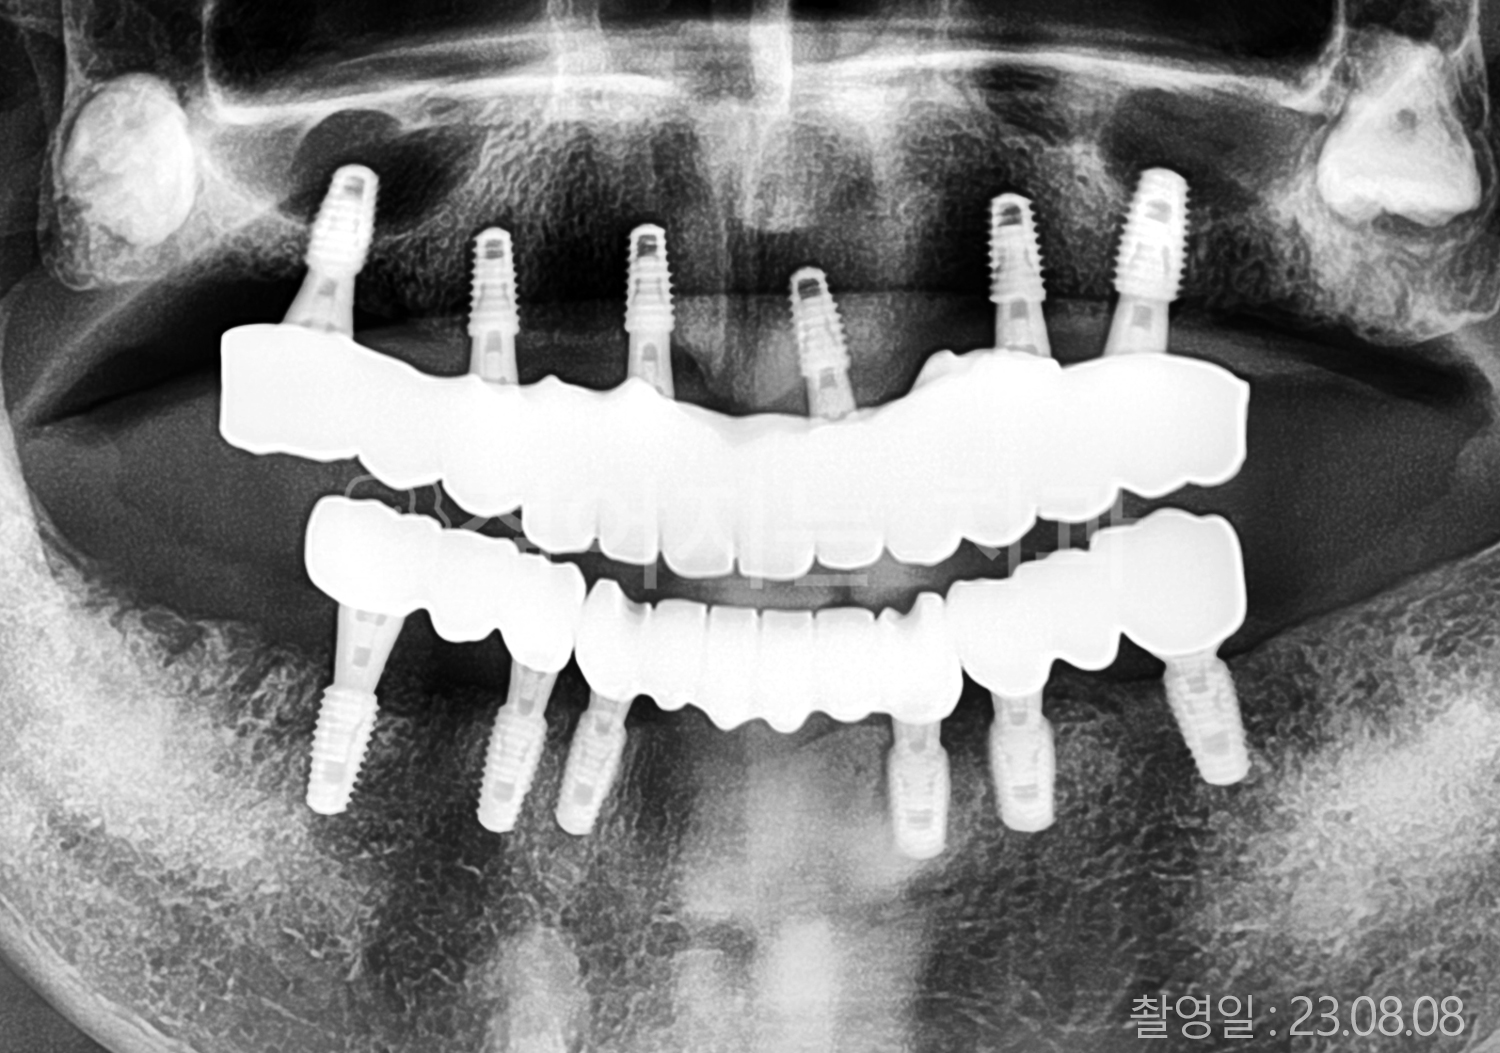

• 50대 고혈압, 당뇨, 고지혈증 전체치아 10개 이상 임플란트

• 60대 골다골증, 간경화 전체치아 10개 이상 임플란트

• 60대 고혈압, 고지혈증 전체치아 10개 이상 임플란트

• 50대 고혈압, 당뇨 전체치아 10개 이상 임플란트

• 60대 고혈압 전체치아 10개 이상 임플란트

• 60대 전체치아 10개 이상 임플란트

• 60대 고지혈증 전체치아 10개 이상 임플란트

• 40대 전체치아 10개 이상 임플란트

• 70대 전체치아 10개 이상 임플란트